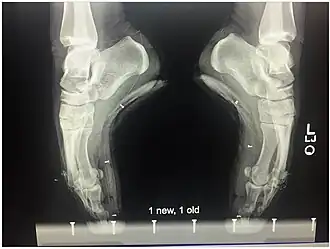

Besonders gefährlich sind schlecht passende oder abgenutzte („tote“) Spitzenschuhe, da diese den Fuß nicht angemessen stützen können,[8] was zu Fehl- und Überlastung führt und die Wahrscheinlichkeit des Umknickens erhöht. Dies kann infolge der unnatürlichen Haltung beim Spitzentanz leicht zu Bänderrissen, Frakturen und diversen Muskelverletzungen führen. Weitere für den Spitzentanz typische Verletzungen sind Entzündungen und Reizungen von Sehnen und Faszien (v. a. Plantarfasziitis, Achillodynie und Extensor Tendinitis), Neuralgien, Ermüdungsbrüche, Verstauchungen der Knöchel und andere Gelenkschäden. Bei entsprechender genetischer Veranlagung, schlecht passenden bzw. abgenutzten Spitzenschuhen und/oder falsch gewähltem Zubehör kann Spitzentanz zudem die Entstehung von Ballen- oder Hammerzehen sowie eines Hallux rigidus begünstigen.[2][9]